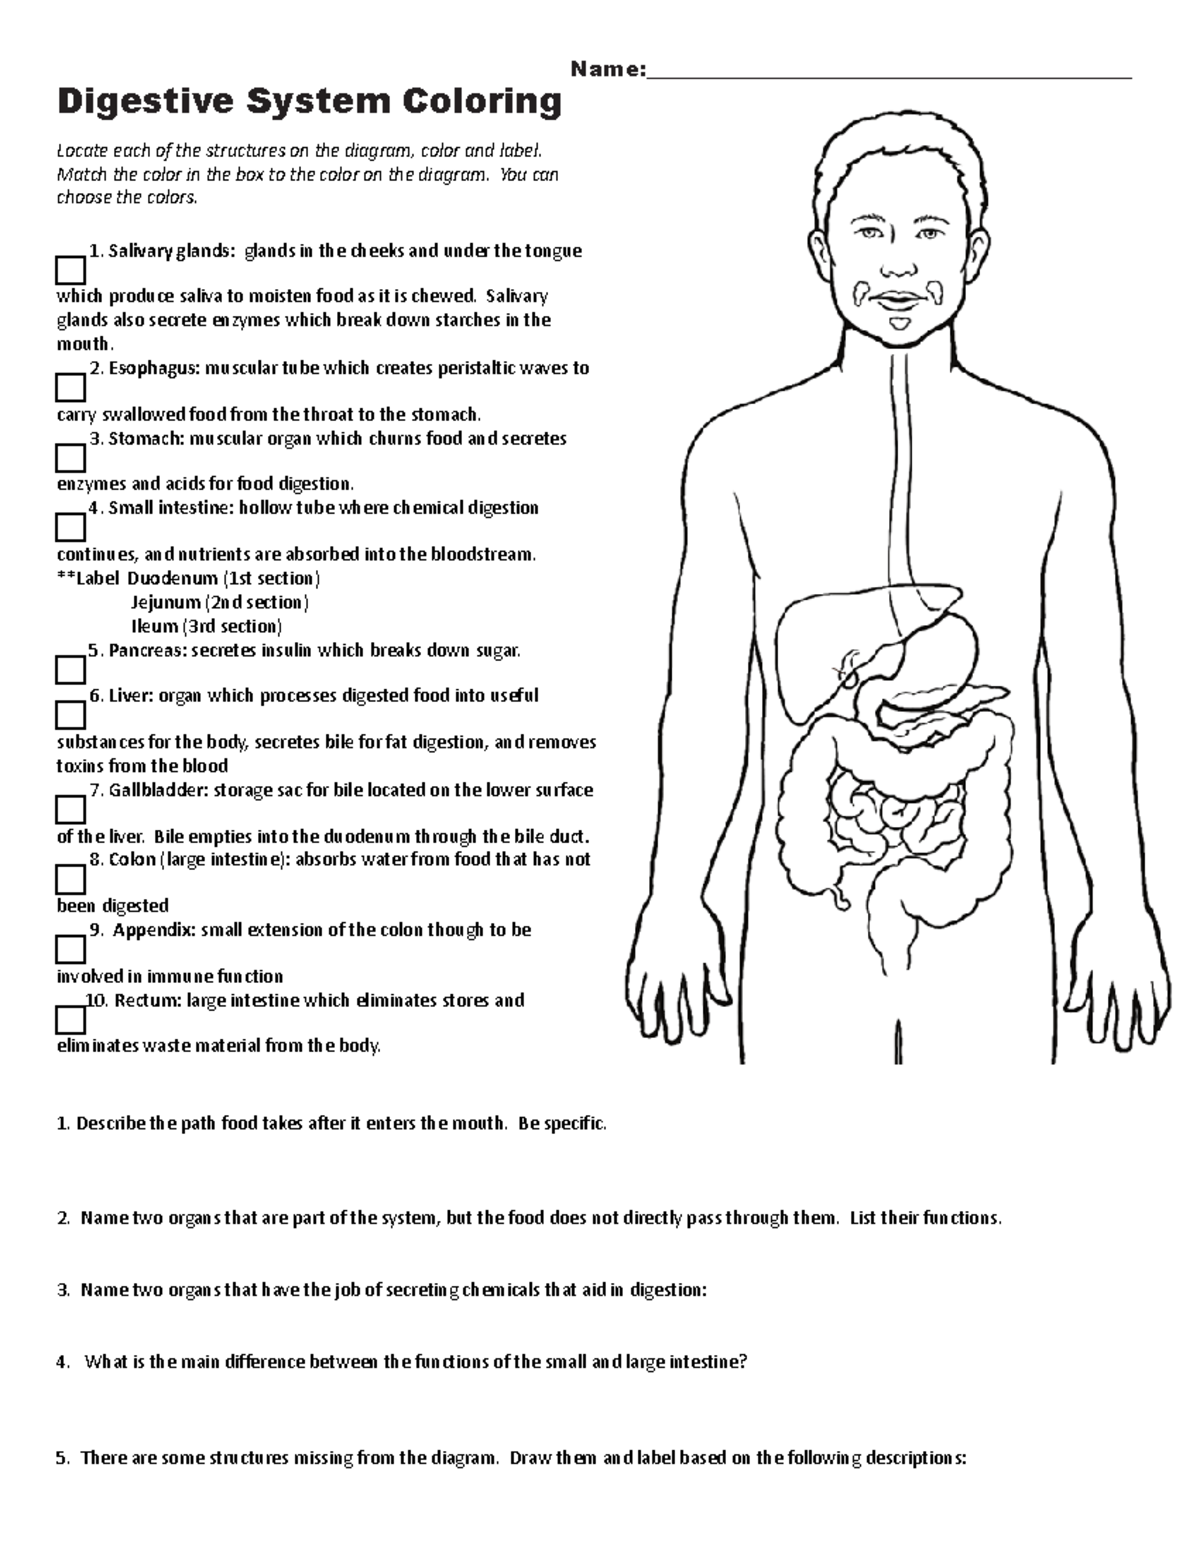

Digestive System Coloring Name

Your digestive tract stretches from your mouth to your anus It includes the organs necessary to digest food absorb nutrients and process waste